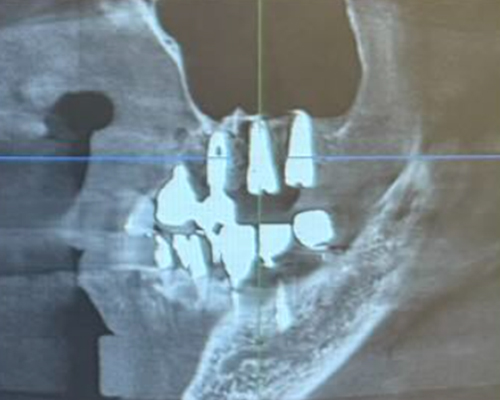

米国の技術×専属技工士×精密機器のフル活用で「短期治療」を実現!

米国の先端治療を安価で

インプラント、マウスピース矯正、小児矯正の歯医者なら「ALBA歯科&矯正歯科」。東京・神奈川・海外を中心に26医院を展開する当グループの専門治療をご案内します。年間1,000症例以上の「世界レベル」オペを実施しているインプラント治療では最安で税込99,800円~の低価格を実現。目立たずメンテナンスも容易と好評の透明なマウスピース矯正は月3,300円からご提供が可能です。重度の歯周病でも徹底的な検査と滅菌で再発を防止し、包括治療で早期解決します。低価格・低リスクの「小児専門」矯正治療を実現、通常100万円ほどかかるワイヤー矯正と比べ、半額程度の費用で矯正治療がおこなえます。年中無休で土・日・祝日も診療中。朝10時台から夜20時(鶴ヶ峰院、上永谷院は19時)まで受診可能。

年間1,000症例以上の 「世界レベル」オペ実施

最安で税込99,800円~の低価格を実現